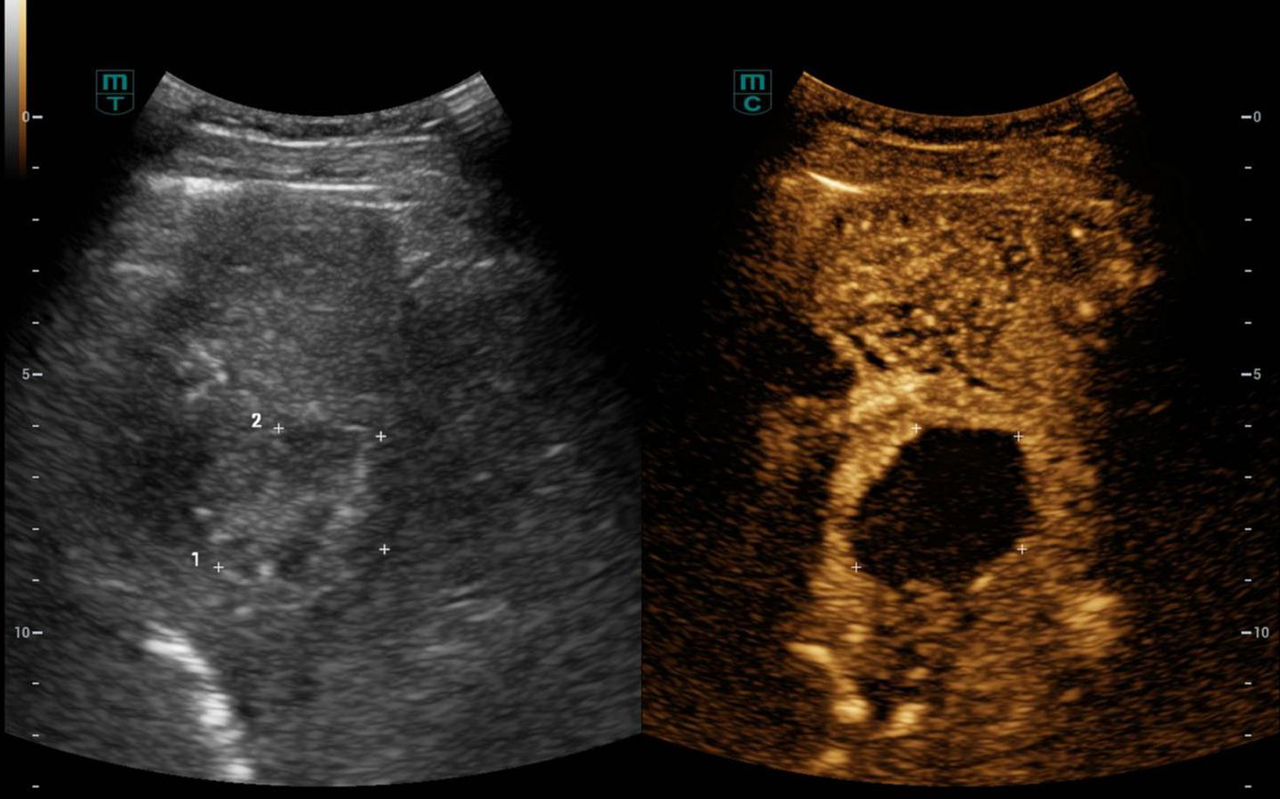

▲ 术后3天超声造影